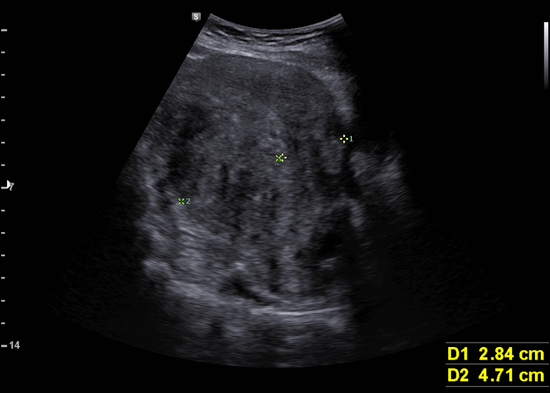

하복부, 골반 초음파; 자궁선근증, 반복되는 빈혈과 방광 압박증상